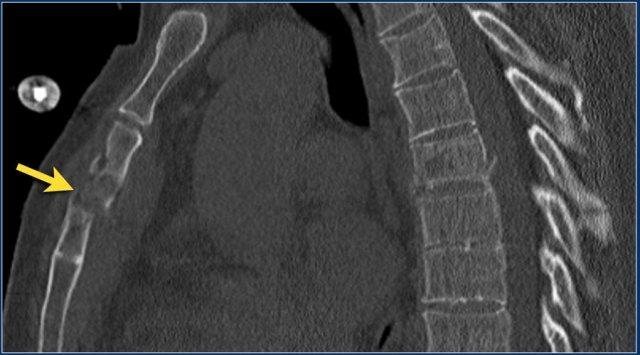

Gãy xương ức

Hình ảnh cho thấy gãy đốt sống kèm gãy ngang mỏm gai, đồng thời có gãy xương ức.

Tương tự như phân loại ba cột của Denis, một số nhà nghiên cứu coi xương ức là cột thứ tư trong gãy xương cột sống ngực trên và xem đây là một biến số độc lập trong đánh giá và điều trị các bệnh nhân này (5).